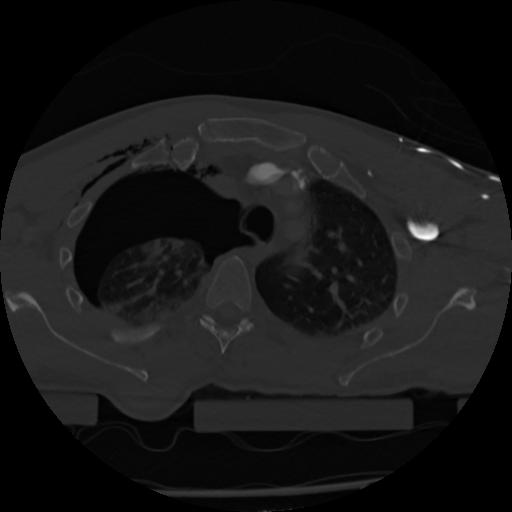

22 ANGIO,CE,Vol,0.5,ANGIO,,